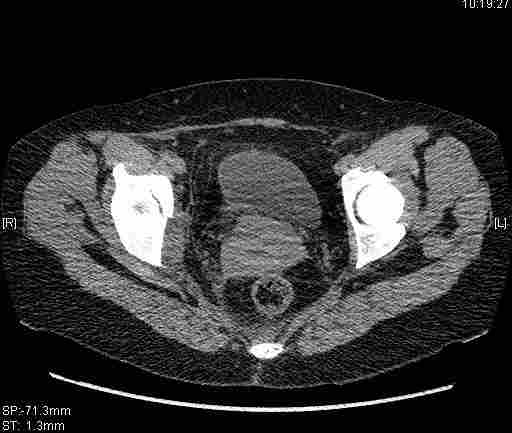

Женщина,58 лет, после ДТП 6 суток. Первично повреждение расценено как переломы ветвей лонной кости. После подтверждения повреждения вертлужной впадины,как чаще всего случается, вопрос встал о тактике. БОльшинство за консерватиное лечение.К сожалению кт у нас "во время" сломался. Прилагаю стандартные снимки вертлужки. У меня следующие вопросы к коллегам:1. Правильно ли рассценивать это повреждение как Т-образный перелом вертлужнй впадины?2. Можно ли добиться анатомической репозиции поверхности вертлужной впадины скелетным вытяжением в данном случае, если нет, что будет этому препятствовать?3. Если смещение останется таким как сейчас, через какое время появится необходимость эндопротезирования (по вашему опыту)?Спасибо.

Удалось сегодня вывести пациентку в соседнюю больницу, где есть кт. Срезы сделаны только горизонтальные.

|

Приветствую,Антон.Рункова рядом нет,но после полученных данных КТ,обсуждали совместно.Итог обсуждения-развернутый ответ дать не получится,т.к.срезы выбраны не информативные.Если ориентироваться на данные 3D,то ,ИМХО,можно лечить на вытяжении.